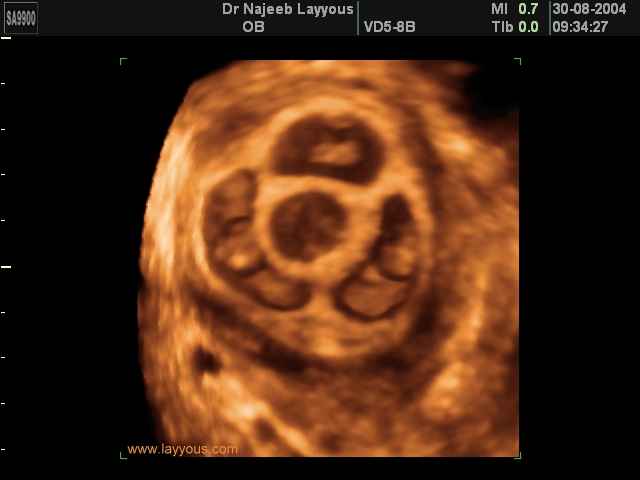

صور لتوائم بجهاز الالتراساوند ثلاثي الأبعاد | الدكتور نجيب ليوس

صور لتوائم بجهاز الموجات فوق صوتية ثلاثي الأبعاد